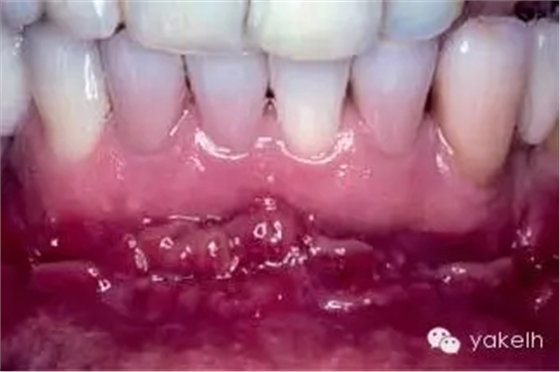

¤¤與口腔頜面部的其他供區(qū)相比,頦部術(shù)后并發(fā)癥的發(fā)生率更高。當(dāng)骨塊以及環(huán)形骨塊移除后,下前牙感覺異常是術(shù)后常見并發(fā)癥。如切牙管神經(jīng)在取骨過程中受損(圖13.24,圖13.25),患者會(huì)感到切牙感覺異常,該損傷通常在6個(gè)月內(nèi)可以自行修復(fù),此時(shí)前牙通常不需要做根管治療。但也會(huì)發(fā)生由于牙髓受損,導(dǎo)致下切牙變色或者繼發(fā)性牙本質(zhì)形成(圖13.26)。即使于前庭溝處做切口,也可出現(xiàn)頦部神經(jīng)感覺異常。骨移植患者發(fā)生頦神經(jīng)感覺異常的幾率較低,但是也有高達(dá)43%的并發(fā)癥發(fā)生率報(bào)道(13.27)。在寒冷的天氣時(shí),頦部氣候功能癥也有報(bào)道。盡管大多數(shù)受損的患者可恢復(fù)正常,但是仍給患者造成困擾。術(shù)前討論可能的并發(fā)癥是明智的,這包括手術(shù)會(huì)導(dǎo)致牙齒以及頦部感覺的異常。盡管未有術(shù)后頦部軟組織外形改變的報(bào)道,但患者往往擔(dān)心該區(qū)域取骨后是否會(huì)影響美觀。影像學(xué)證據(jù)表明,在一些老年患者中,供區(qū)骨空腔不能完全修復(fù)。用可吸收的骨替代品,如骨庫骨或者小牛骨充填供區(qū)的缺損,可以減少患者的疑慮。術(shù)后沒有發(fā)生過頦部下垂,但為防止頦部下垂,在取骨時(shí)應(yīng)避免把下頜骨上的組織完全撕脫。曾有報(bào)道在取骨后,下頜骨剩余舌側(cè)骨板發(fā)生骨折。如前所述,這可能是取骨時(shí),太靠近下頜骨邊緣所造成的。頦部取骨的術(shù)后疼痛比較明顯。術(shù)后應(yīng)用長(zhǎng)效局麻藥,如布比卡因行下頜神經(jīng)阻滯麻醉,可以延遲疼痛的發(fā)生,以便人體有充分的時(shí)間來吸收止痛藥。術(shù)前應(yīng)用非甾體類藥物,如布洛芬等可減少疼痛和腫脹。

圖13.27 頦部取骨后的神經(jīng)感覺減退。